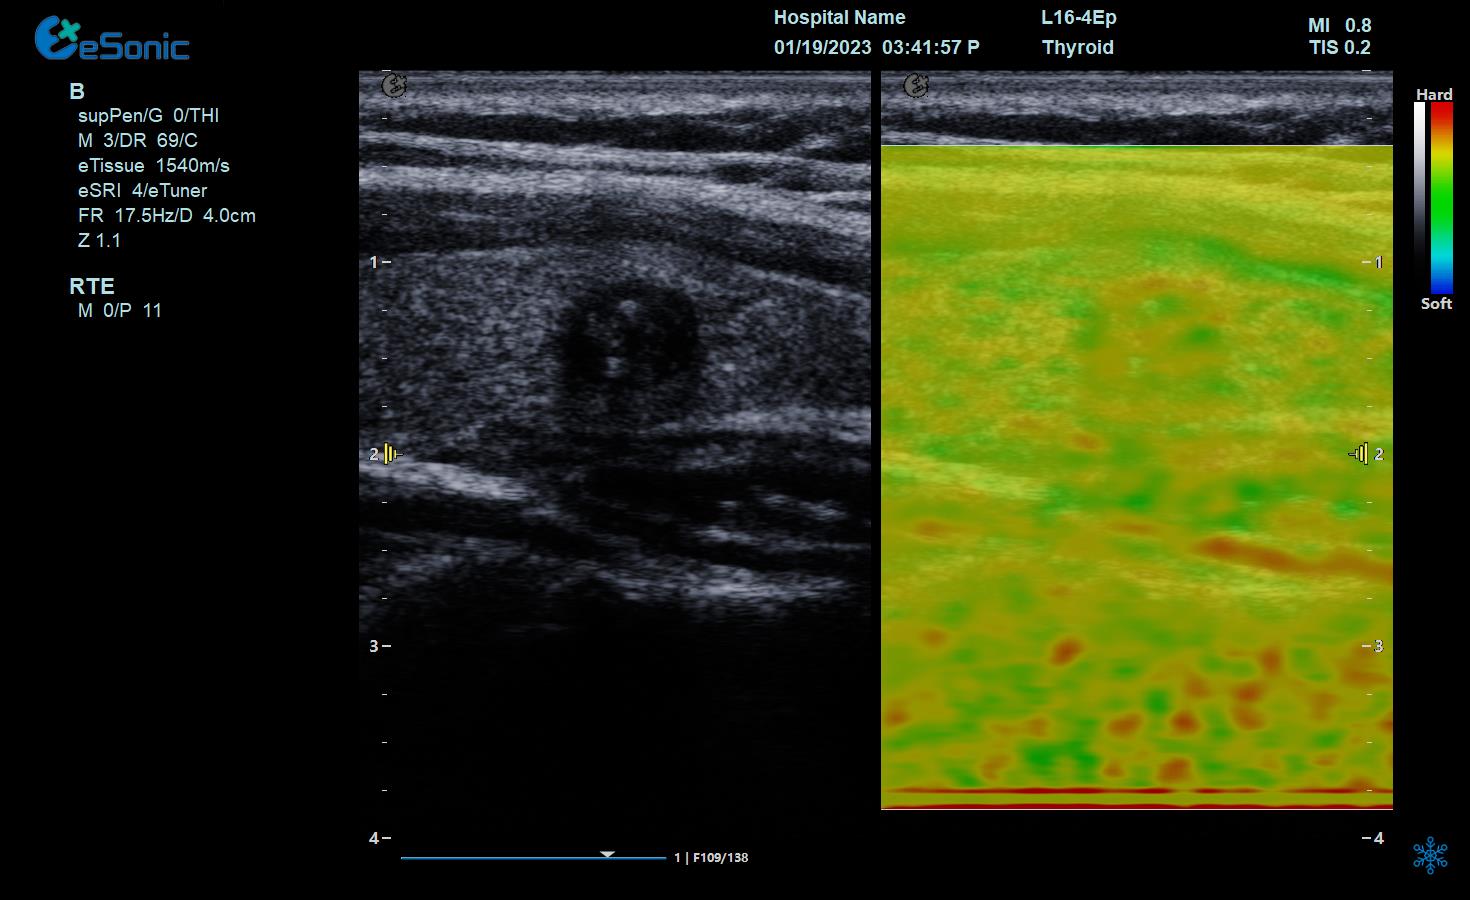

实时弹性成像